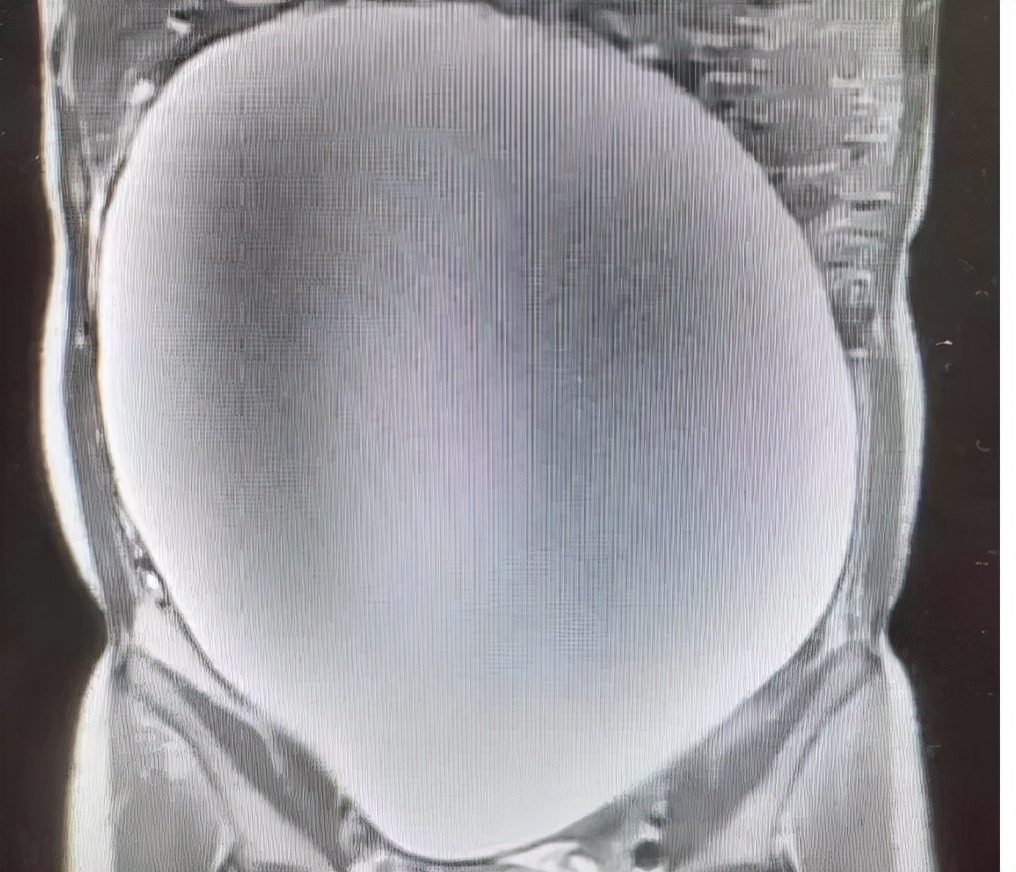

她急忙来到厦门市第五医院求诊,经腹部磁共振一扫检,肚子里竟然藏了个巨大的卵巢肿瘤,直径足足30CM大。

核磁共振扫描结果 图源:厦门广电

幸运的是,经过术中快速病理,发现该肿瘤为良性肿瘤,医生成功地做了手术将肿瘤切除了。